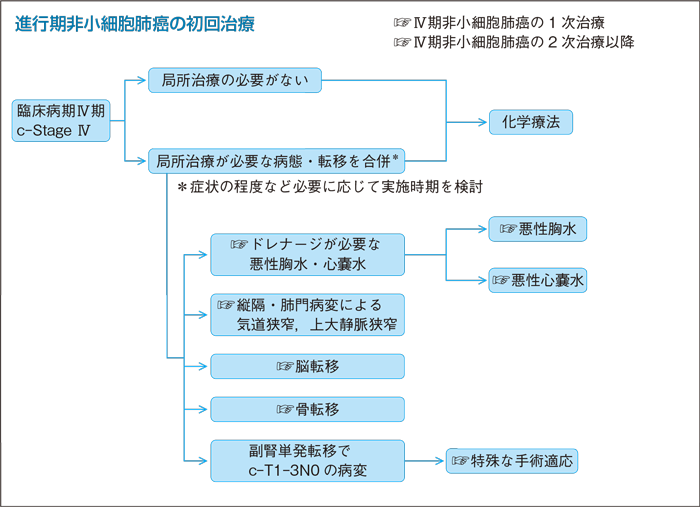

進行肺がん 新薬続々 分子標的薬や免疫薬 ヘルスup Nikkei Style